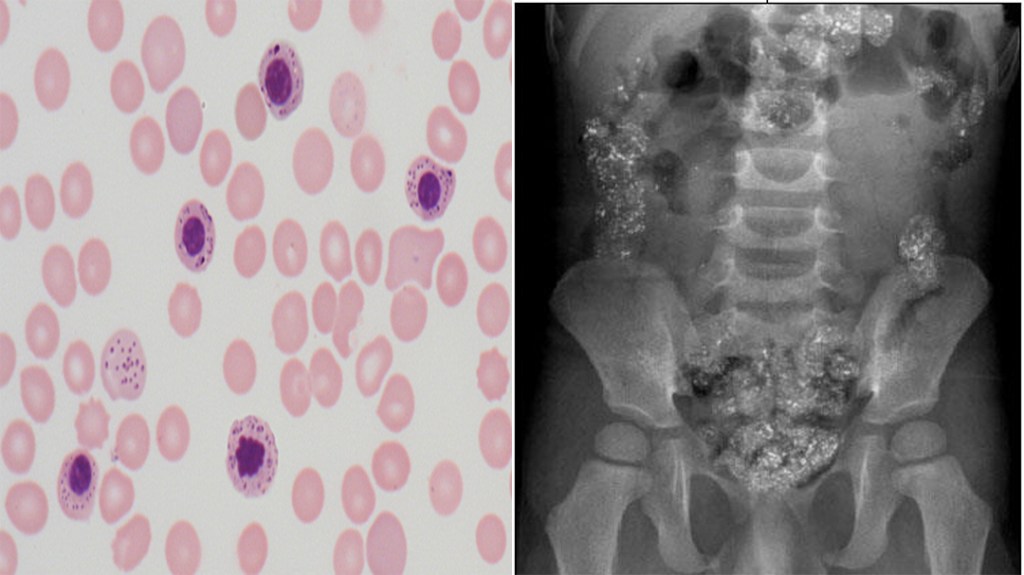

A 2yr old child is brought to the ED for altered mental status, vomiting, and lethargy. The parents states that this has been occurring since they moved into their grandmother’s home 2 months ago. Vitals signs are within normal limits and CBC reveals a hemoglobin – 10.1 mg/dL, mean corpuscular volume (MCV) – 71 fL/cell, and mean cell hemoglobin concentration (MCHC) – 29.1 g/dL. Peripheral smear and abdominal xray are below.

- The peripheral smear reveals stippling and granules in the basophils and the abdominal radiograph shows hyperlucent flecks throughout the colon. These findings with the history of living in a older home leads to the most likely diagnosis of lead intoxication from eating the chipped paint.

- The next diagnostic step for lead intoxication is to send a blood lead level for confirmation, as well as a serum erythrocyte protoporphyrin. Given his AMS, he should also have a non-contrasted head CT.

- Management of children with lead intoxication is directed by the lead levels. First and foremost, you should contact your regional poison center for guidance by a pediatric toxicologist. For our patient, he is symptomatic and management includes fluid administration, possible whole bowel irrigation (though lead is not absorbed in the colon), and chelation therapy with succimer and calcium disodium edetate.